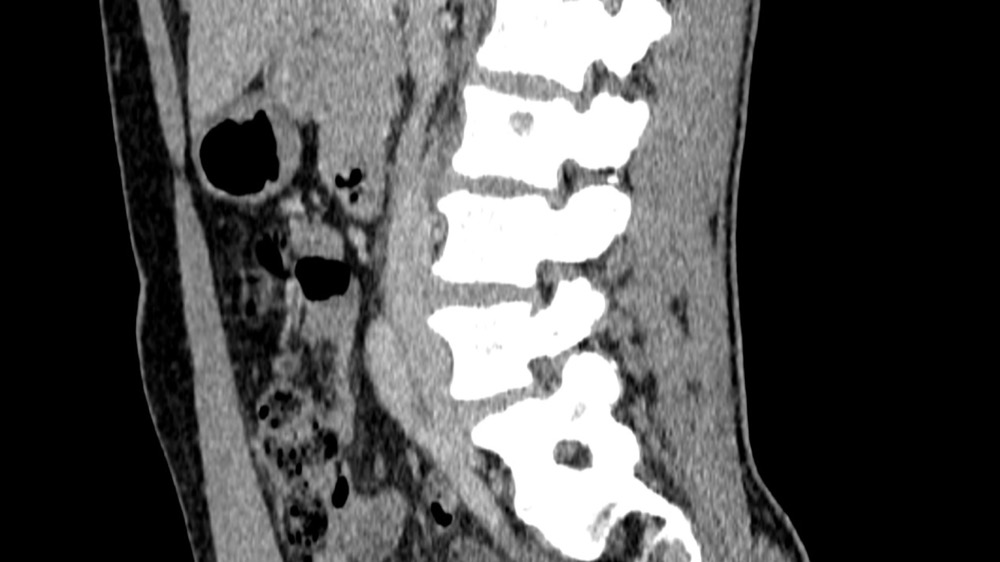

Constance du Boisbaudry 19/01/2022